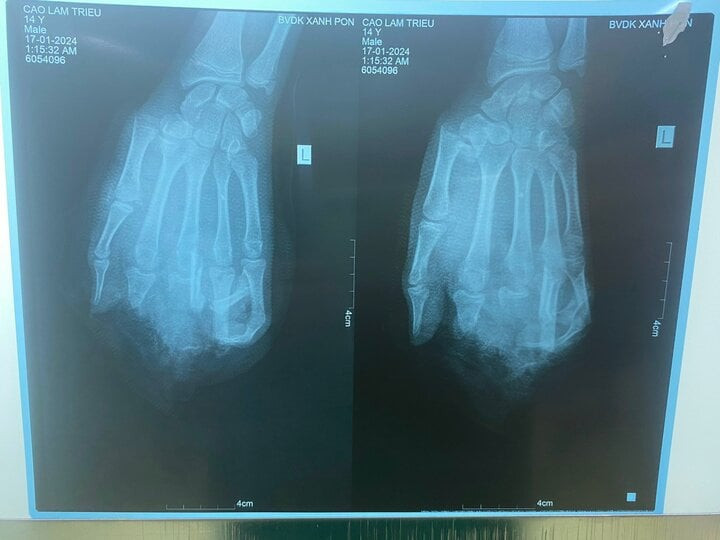

| Ảnh chụp X-quang bàn tay dập nát của bệnh nhân. Ảnh: BVCC |